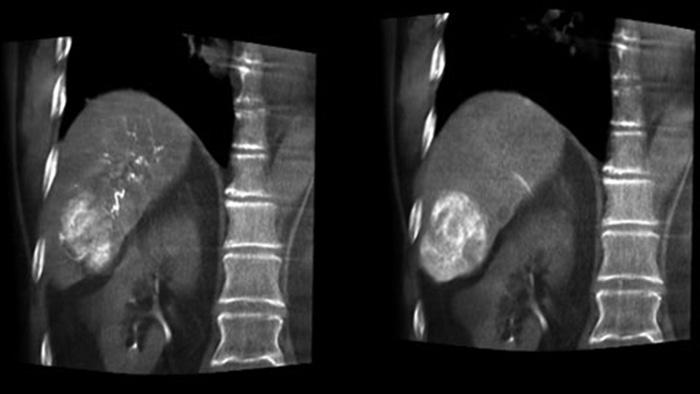

塞栓術後の3D画像収集では、腫瘍内のリオピドールや放射線不透過ビーズなどの塞栓物質の蓄積状態を視覚化できます⁵。

Dual Viewでは、塞栓術前の動脈相3D画像と塞栓術後の画像を同時に表示して、治療エンドポイントを評価できます。